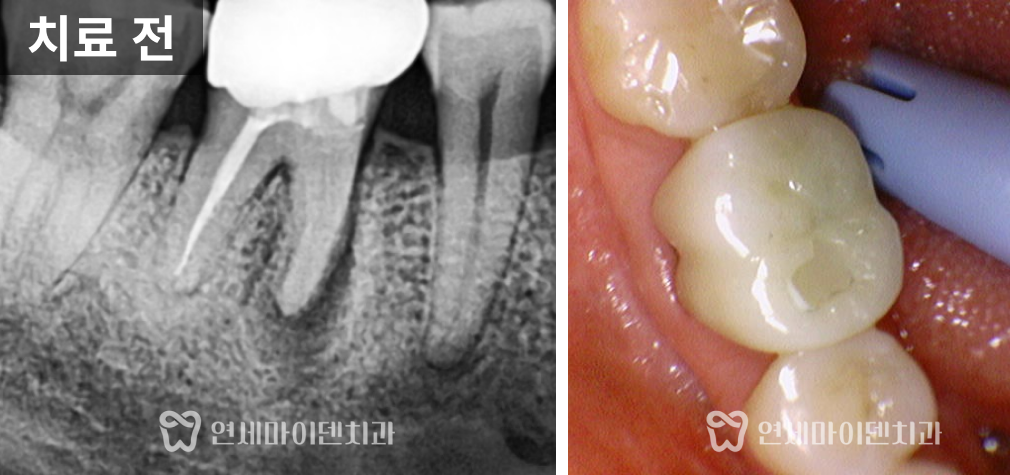

반대편 어금니(#46)는

스플린트 크라운으로 수복되어 있었습니다.겉으로 보기엔 멀쩡했지만,

내부에는 깊은 충치가 진행돼 있었습니다.보철물을 제거하자 치아 내부 조직이 심하게 손상되어 있었고,

결국 보존 불가로 판단했습니다.

이에 따라 발치 후 즉시 임플란트를 진행했습니다.

다행히 치조골 상태가 양호해 즉시 식립이 가능했습니다.

임플란트 식립 후 골이식과 멤브레인 적용을 통해 뼈의 안정화를 유도했고,

2주 뒤 봉합사 제거 후 출국하실 수 있도록 계획했습니다.최종 보철물은 귀국 시기에 맞춰 맞춤 제작하여 완성했습니다.

💡 스플린트 크라운(여러 치아가 묶인 형태)은

청결 관리가 어렵고, 내부 충치가 생겨도 확인이 늦을 수 있습니다.

이후에는 단독형 크라운으로 교체하여 관리 효율을 높였습니다.